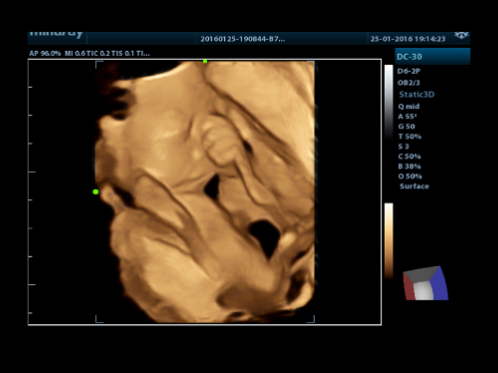

Standard ultrasound systems available today typically allow for a basic diagnosis but lack advanced functionality. Now, with the most competitive price in the industry, the DC-30 is the perfect answer for high quality image performance, with added features such as 4D imaging with iPage.

iPageTM

A CT-like view functionality displaying volume data in multiple parallel 2D images to effectively interpret anatomical structures.